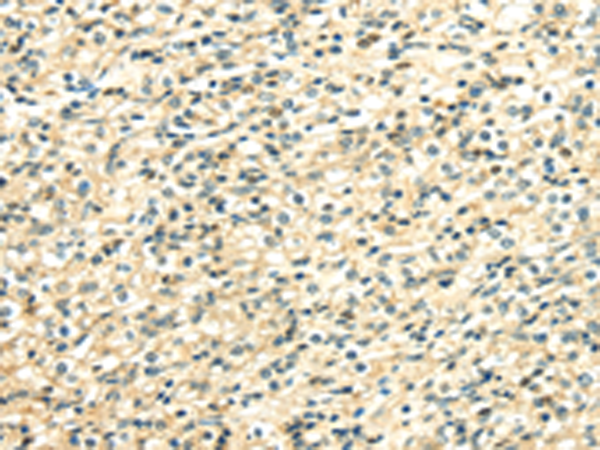

分类: 科研抗体货号: P08839别名: HDL4; GTF2D; SCA17; TFIID; GTF2D1应用: WB,IHC反应种属: Human